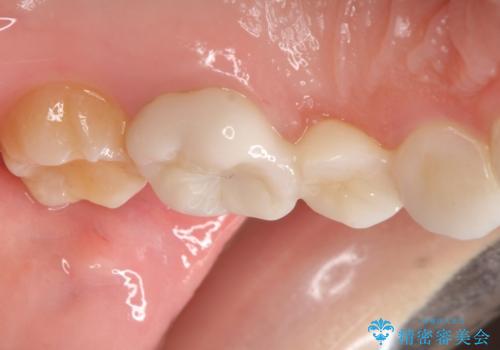

- 昔装着したかぶせ物が、不自然なのでやりかえたいとのことで来院されました。

前歯にレジン前装冠(保険内)が装着されており、自然な透明感がありません。

また奥歯にまたがるブリッジも金属のもので、適合もよくありませんでした。

オールセラミックによるやりかえを行いました。

色調もまわりの歯に合わせて、形態も患者様のご希望に沿うように製作させていただきました。